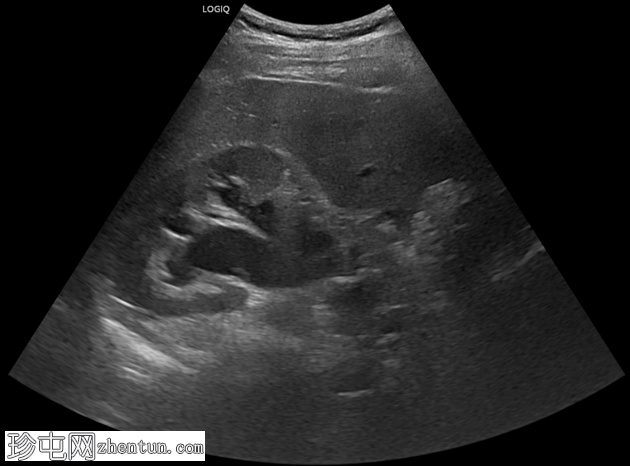

患者主诉急性绞痛性腰痛,放射至腹股沟。

年龄:30岁

性别:男

超声

检查

斜位

纵位

右侧中段输尿管结石,大小约1厘米,呈高回声,伴有声影,并可见闪烁伪影,导致中度右侧肾积水。